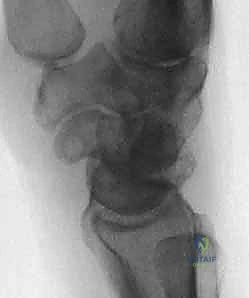

- التصوير بالأشعة السينية (X-rays): يتم أخذ صور شعاعية في وضعيات متعددة (أمامية خلفية، جانبية، وبقبضة مغلقة Clenched Fist View). وضعية القبضة المغلقة تزيد الضغط على المفصل وتُظهر بوضوح الفجوة بين العظمين (علامة تيري توماس) إذا كان الرباط ممزقاً.

يُسبب تشوه DISI، الذي يتميز بتمدد العظم الهلالي غير المرتبط وانثناء الزورقي، اتساعًا واضحاً في المسافة الزورقية الهلالية (تُعرف إشعاعياً بعلامة تيري توماس "Terry Thomas sign") وتغييراً جذرياً في حركية الرسغ. إذا تُركت هذه الحالة دون علاج احترافي من قبل طبيب متمرس كالدكتور محمد هطيف، فإنها تؤدي حتماً إلى هجرة العظم الرأسي (Capitate) للأسفل بين العظمتين المنفصلتين، مما يطلق سلسلة من التآكل الغضروفي السريع الذي ينتهي بـ الانهيار المتقدم للرسغ الزورقي الهلالي (SLAC wrist)، وهي حالة تتطلب جراحات إنقاذية كبرى مثل دمج مفصل الرسغ.